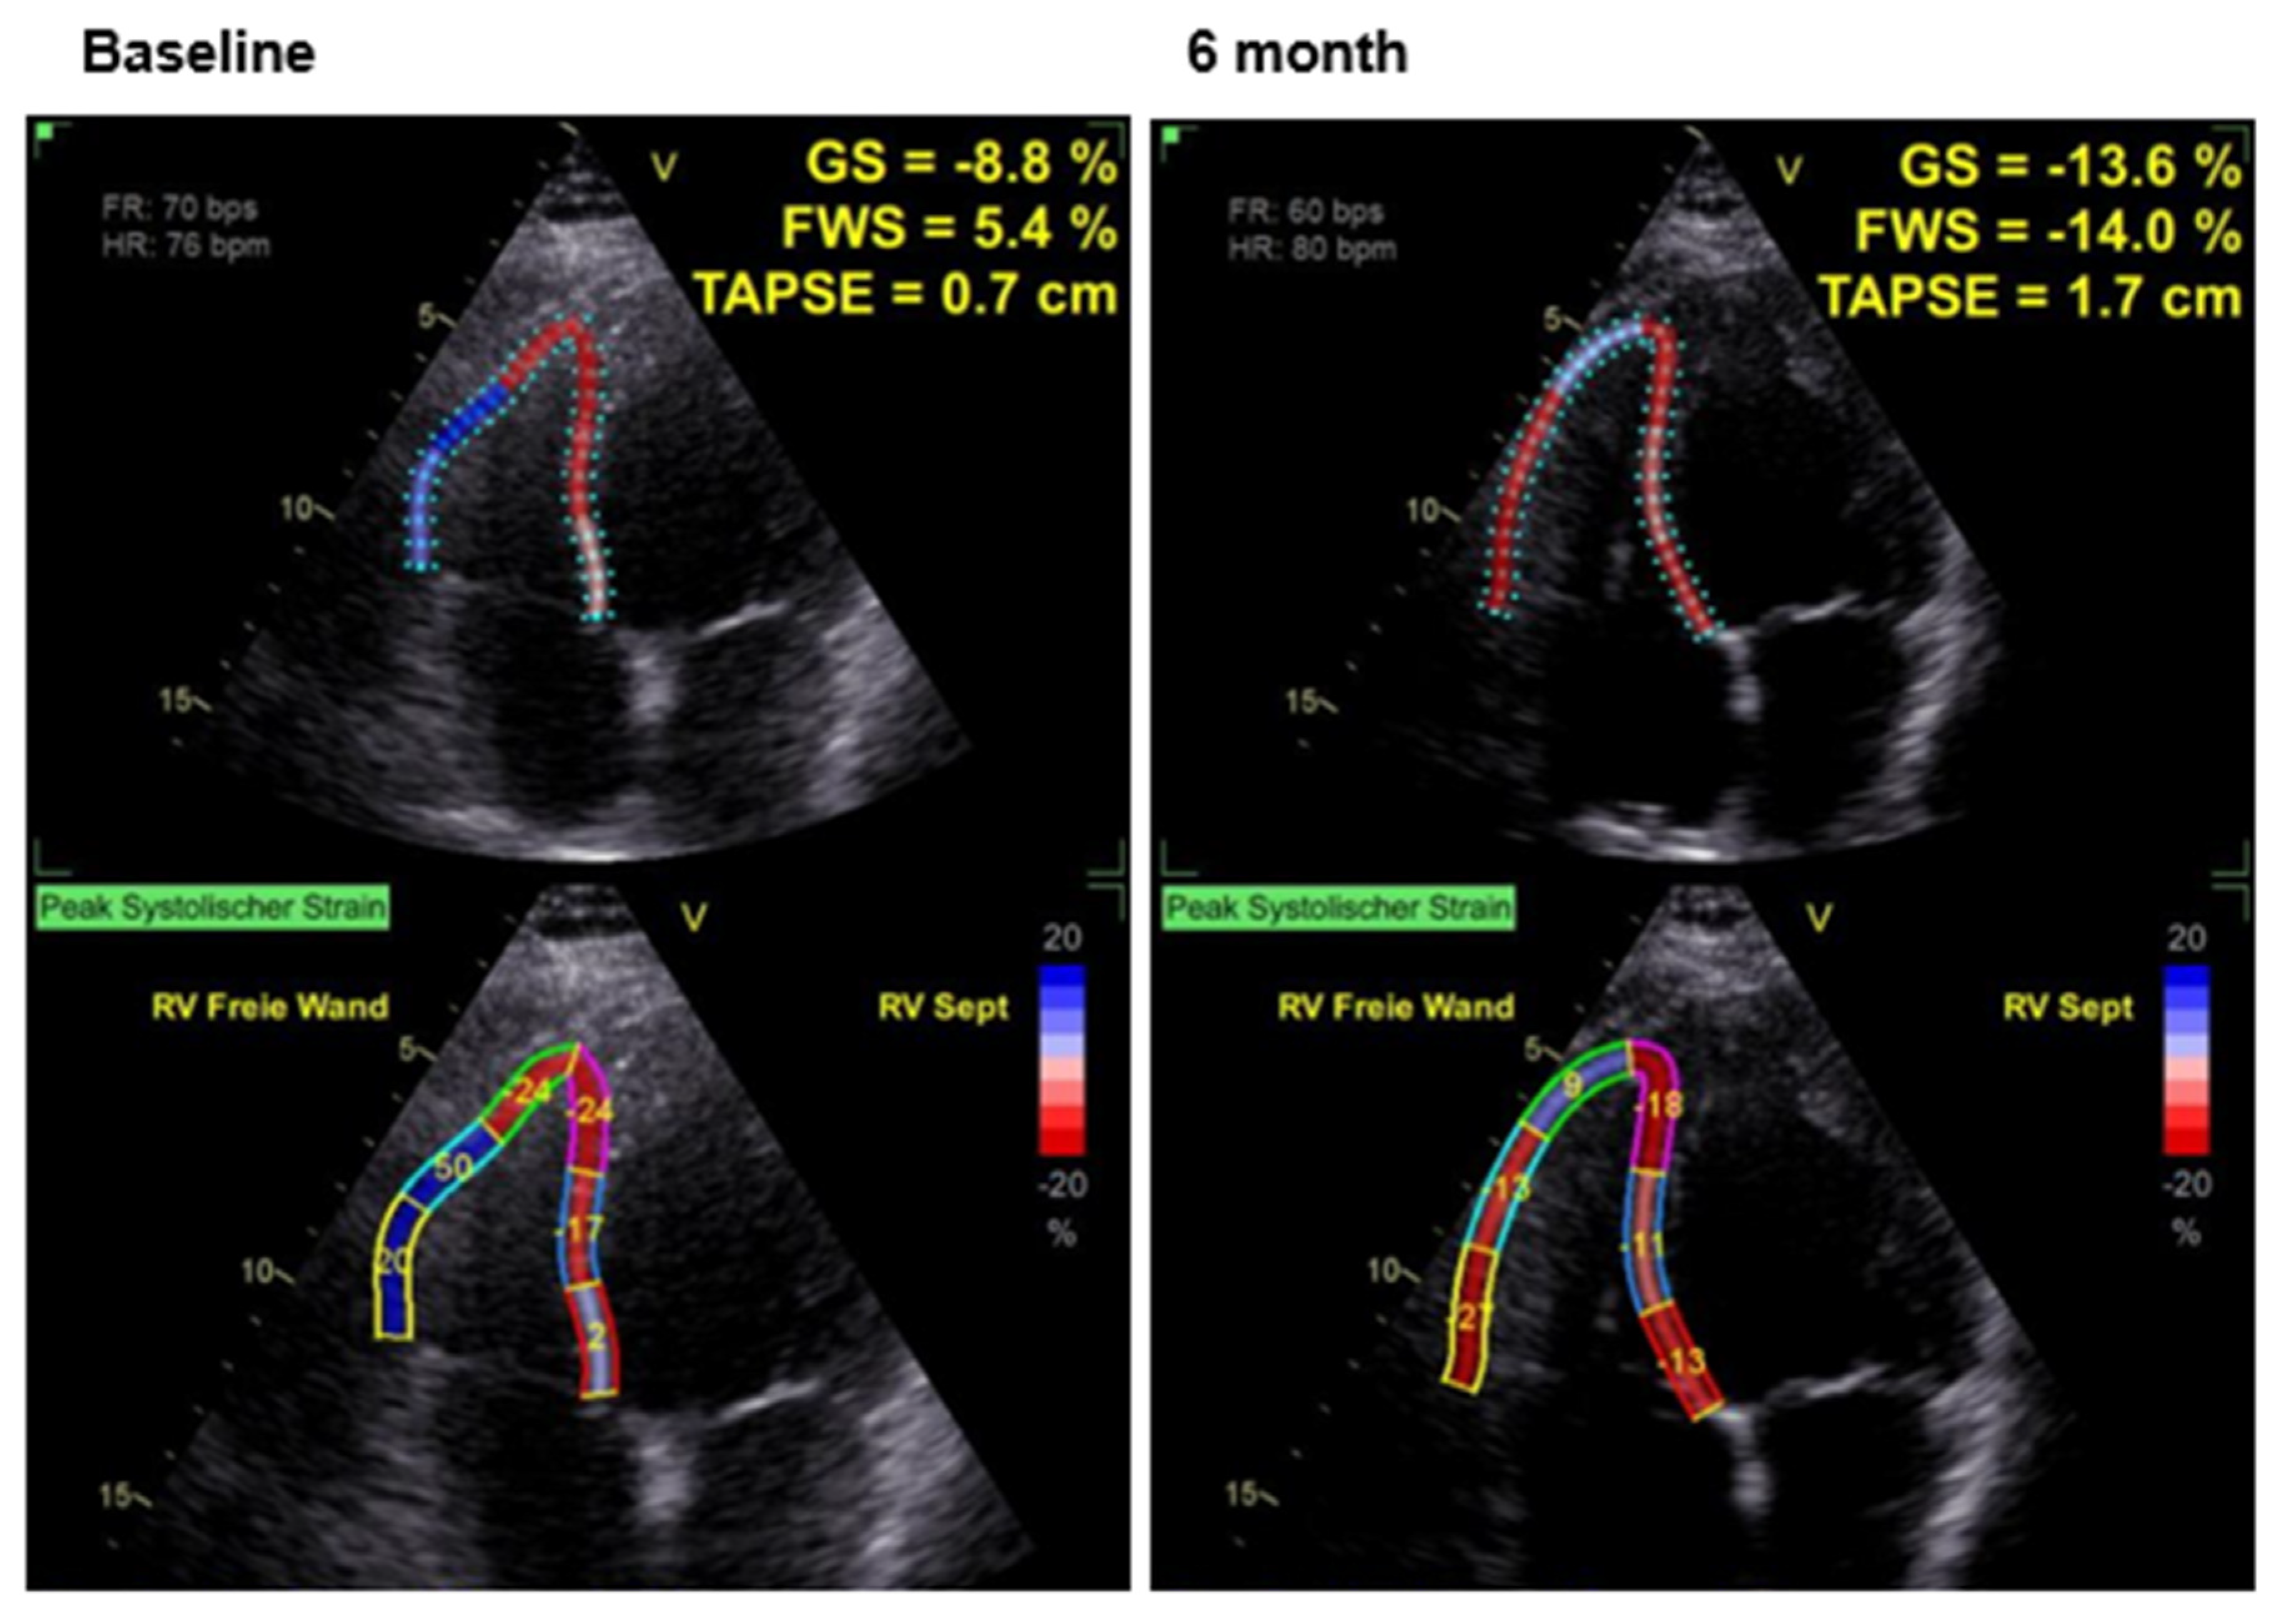

Effects of CCM Therapy

| RV GS [%] | −13.7 ± 4.5 | −10.1 ± 5.0 | <0.05 |

| FWS [%] | −14.6 ± 7.3 | −10.3 ± 10.2 | <0.05 |

| TAPSE [mm] | 18.8 ± 5.1 | 17.6 ± 5.6 | n.s. |